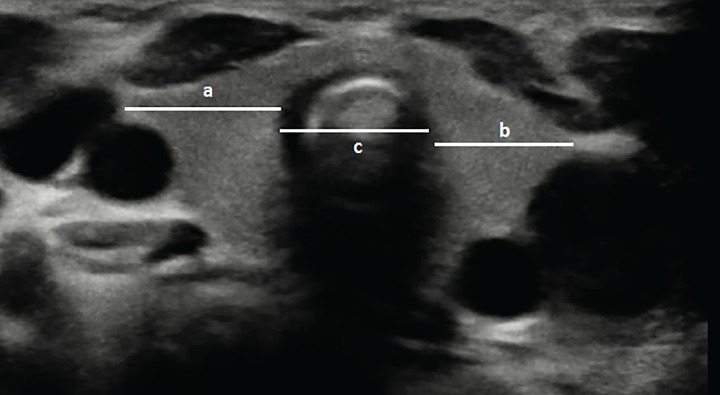

Methods: Thyroid imaging was performed at 0-2 days and 15-30 days using handheld and portable ultrasound (US) devices. Thyroid volume and tracheal index were calculated using standard formulae.

Results: A total of 144 healthy, term newborns with a mean birth weight 3230 g were enrolled. The normal thyroid volume for the entire population was 0.66±0.25 mL at 0-2 days, which significantly increased to 1.12±0.33 mL at 15-30 days (p<0.01). There were no significant differences in thyroid volume between genders in either age group (p=0.246 and p=0.879). Thyroid volume correlated with birth weight, length, and head circumference, with the strongest correlation being with birth weight (r=0.404, p<0.001; r=0.252, p=0.002; r=0.223, p=0.007, respectively). The tracheal index at 0-2 days was 1.84±0.30 in girls, 1.82±0.27 in boys, and 1.83±0.29 overall. At 15-30 days, it was 1.99±0.23 in girls, 2.00±0.28 in boys, and 1.99±0.25 overall. Similar to thyroid volume, the tracheal index increased significantly with age (p<0.01), with no significant gender differences in either age group (p=0.593 and p=0.886). Thyroid volume and tracheal index were moderately correlated in both measurements (rho=0.538, p<0.01). Measurements of the trachea, and thyroid lobe widths using portable and handheld US devices were positively correlated (r=0.449, p<0.01; r=0.638, p<0.01; r=0.497, p<0.01). There was also a correlation between tracheal index measurements using both devices at both the first and second measurements.